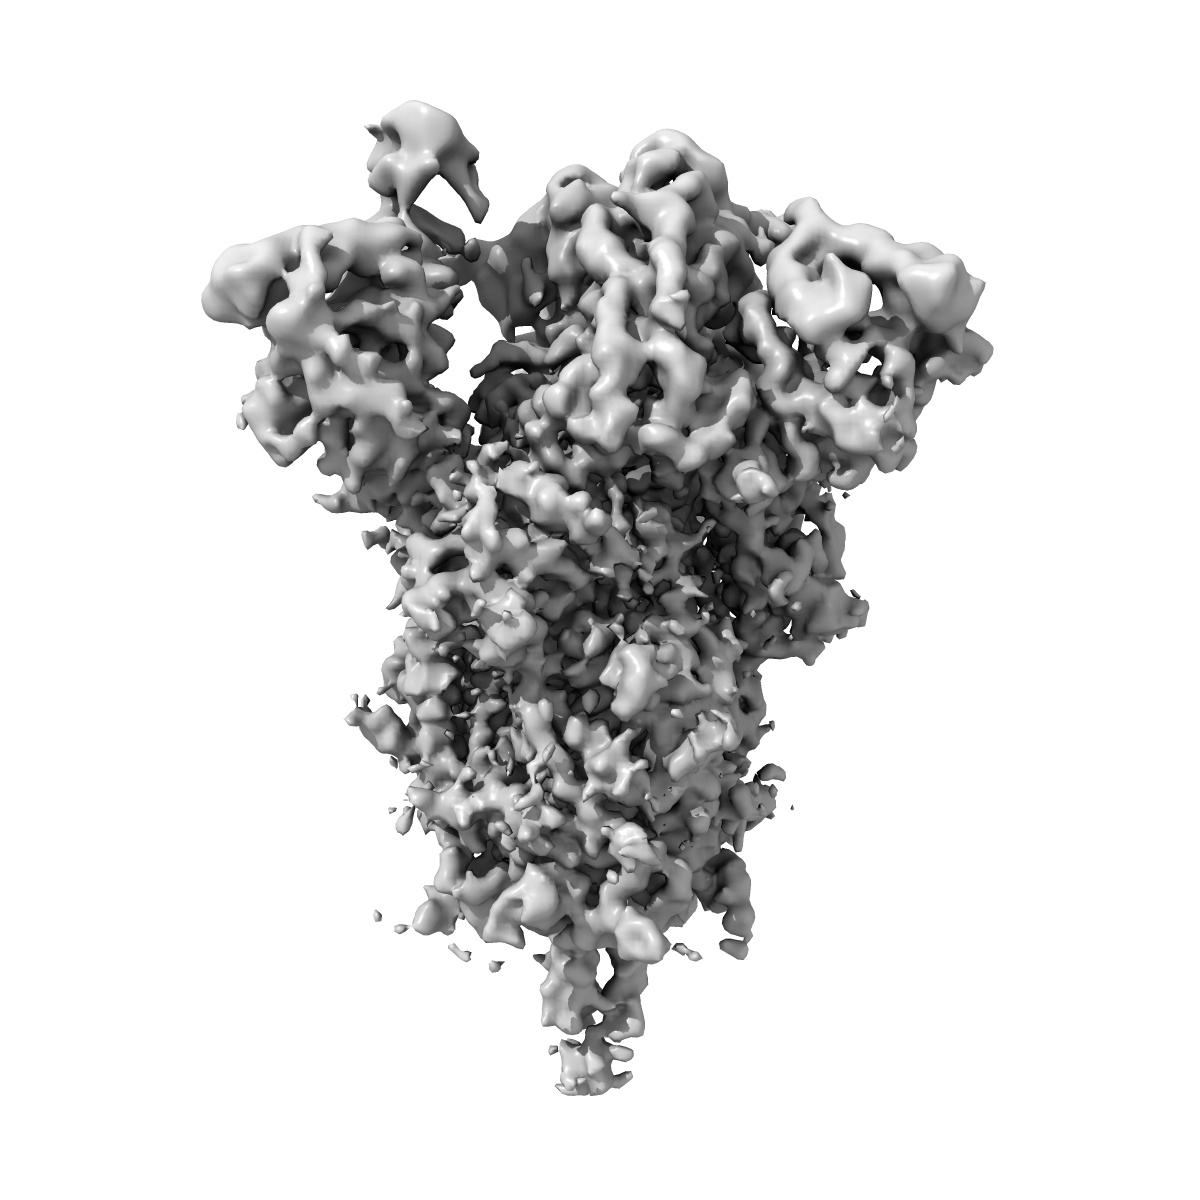

Cryo-EM structure of SARS-CoV-2 Spike Proteins on intact virions: Alpha (B.1.1.7) variant 1 open RBD

Virion morphology and on-virus spike protein structures of diverse SARS-CoV-2 variants.

Ke Z , Peacock TP , Brown JC , Sheppard CM , Croll TI , Kotecha A , Goldhill DH , Barclay WS , Briggs JAG

(2024) EMBO J , 43 , 6469 - 6495